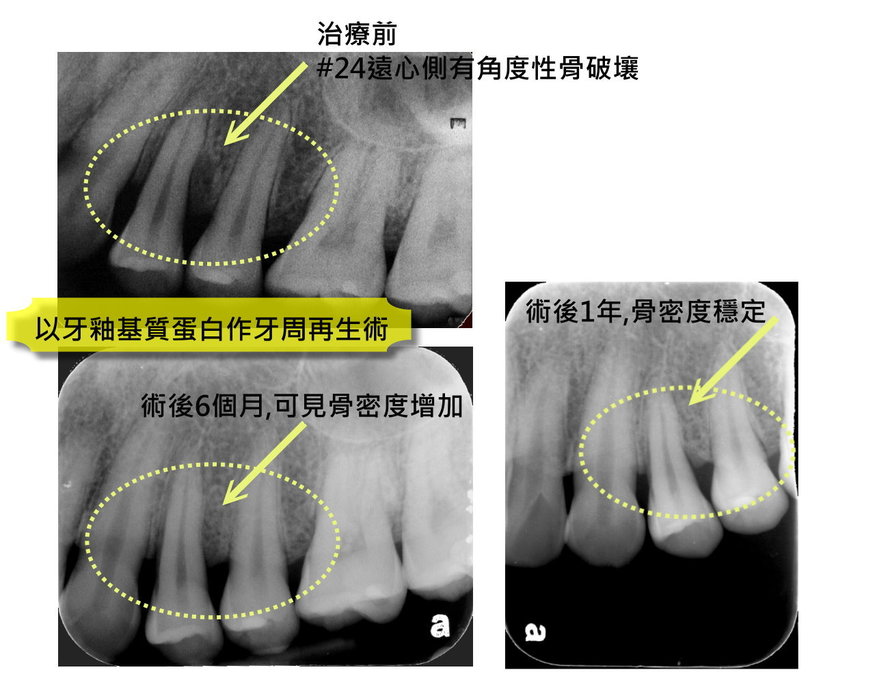

牙周治療

案例二